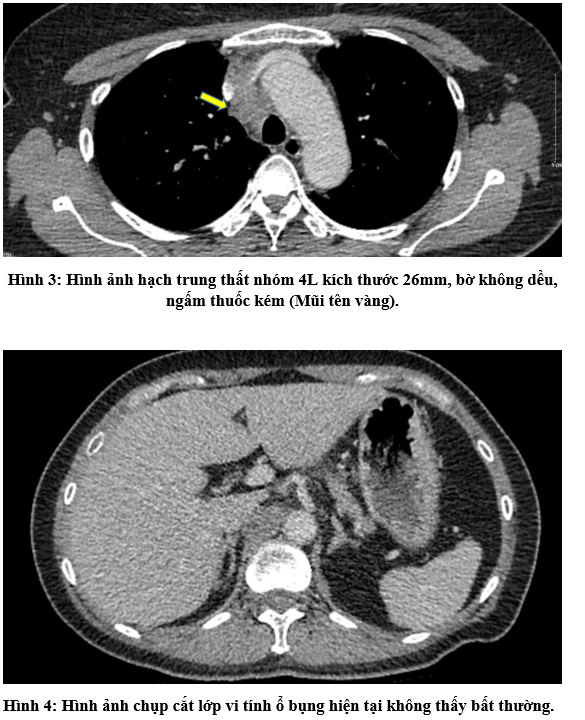

CASE LÂM SÀNG Điều trị bệnh nhân mắc đồng thời hai loại ung thư: Ung thư phổi và ung thư tuyến tiền liệt

CASE LÂM SÀNG Điều trị bệnh nhân mắc đồng thời hai loại ung thư: Ung thư phổi và ung thư...